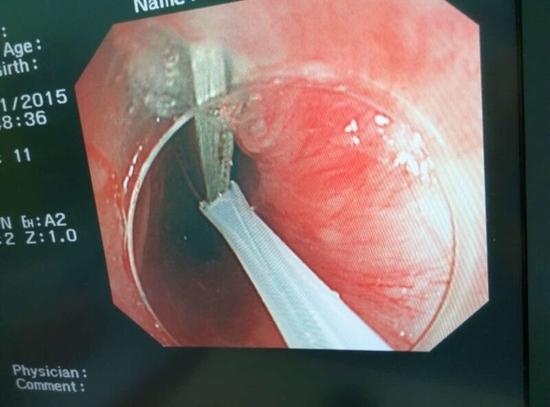

醫(yī)生從華先生胃里取出的鑷子和打火機

手術(shù)中,范醫(yī)生通過胃鏡準(zhǔn)確發(fā)現(xiàn)了胃里的鑷子。但讓他驚訝的是,在華先生胃底竟然還躺著三個被腐蝕了的打火機,打火機的金屬部件都已經(jīng)不見了。

隨后,范醫(yī)生先用圈套器套取出了長10厘米的鑷子,再一個一個地取出了打火機。整個取出過程小心謹慎而又一氣呵成,只用了不到10分鐘。